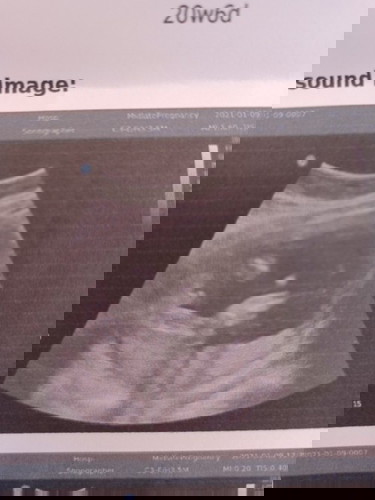

นอนไม่อายหมอเลยลูกแม่ ... นู๋นอนอ้าซ่ะขนาดนั้น แม่ไม่ได้ลุ้นเลยจร้าาาาา #ท้องแรกคะ

ดูไม่เป็นเลย😁อันนี้คือช่วงก้นน้องหราคะ

ใช่ค่ะ ก้นน้องแล้วจู๋โพล่ที่แหลมๆค่ะ